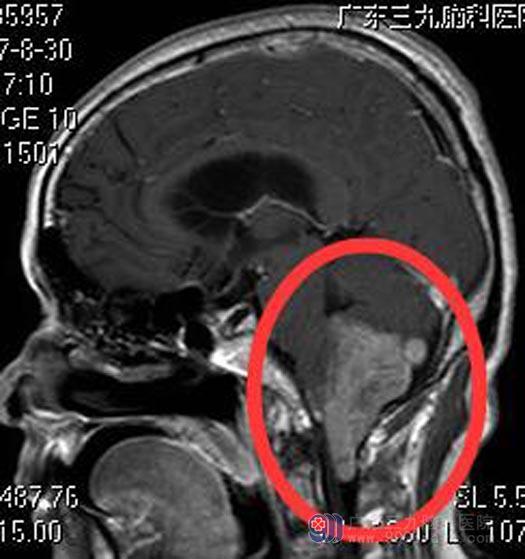

广东三九脑科医院头部CTA检查:1.小脑下蚓部区占位性病变血供较丰富,考虑肿瘤性病变,建议MRI平扫+增强进一步检查;2.双侧大脑后动脉异常改变,考虑动脉硬化;其中双侧颈总动脉斑片状低密度影,考虑低密度软斑块或内膜增厚可能。颅脑MRI平扫+增强提示:右侧枕骨大孔区占位性病变,范围约为5.0cm×4.4cm×3.8cm,延髓、颈髓受压稍向前移位;第四脑室正中孔受压变窄,以上脑室系统明显扩大,室旁示斑片状间质水肿影。可能为孤立性纤维瘤/血管外皮细胞瘤,待排脑膜瘤。

人的呼吸中枢和心血管中枢在脑干延髓中,手术稍有不慎损伤到中枢就会有生命危险,手术风险很大,对医院设备和手术医生技术要求都非常高。骆先生和家属都积极要求手术治疗。由综合神经外科鲁明主任主刀,在全麻下行延髓、四脑室巨大占位切除术,术中显微镜下见灰褐色肿瘤组织,位于右侧延髓腹外侧,肿瘤质软,血供一般,肿瘤基底部与副神经、舌咽神经、迷走神经粘连紧密,予小心分离后切除,过程中副神经、舌咽神经、迷走神经、小脑后下动脉均保留完整,肿瘤全切,手术顺利。术后神志清醒,生命体征平稳,无后组颅神经损害症状。病理回报:室管膜瘤 WHO II级。